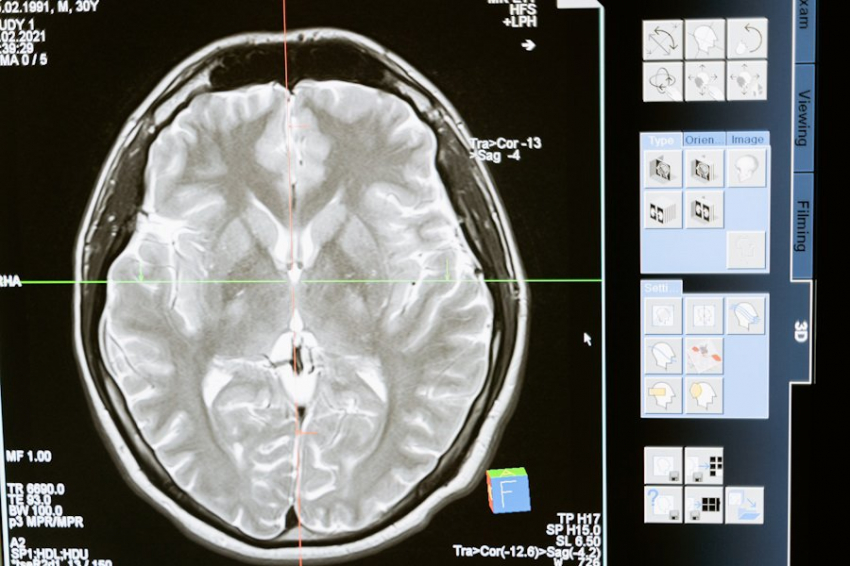

Ученые определили, как характер способствует развитию слабоумия

Исследования психологов Калифорнийского университета, опубликованные на портале Alzheimer's & Dementia, указывают на потенциальную связь между личностными чертами и риском развития деменции.

Исследователи проанализировали данные 44 000 участников, выявив тесную связь между личностными качествами и риском деменции. Участники с высокими баллами по отрицательным чертам личности, таким как негативный аффект и невротизм, имели более высокий риск развития деменции, в то время как те, кто имел более высокие баллы по положительным чертам, например, добросовестности и позитивному аффекту, имели более низкий риск.

Учёные отмечают, что небольшие изменения в личностных чертах могут существенно снизить риск деменции. Например, увеличение уровня добросовестности на 10% связано с 15-кратным снижением риска.

Однако, важно отметить, что характерные признаки деменции в мозге не обязательно соответствуют проявлению симптомов. Это подчеркивает сложность понимания и лечения деменции.